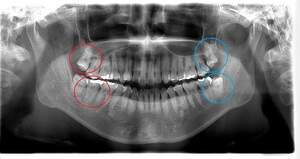

左上下の親知らずが

大きな虫歯になっていた症例

- 抜歯前写真(レントゲン)

- 抜歯前写真(CT画像)

| 年齢 | 20代・男性 |

|---|---|

| 主訴 | 奥歯が欠けて、痛みがある |

| 親知らずの生え方 | 完全に出ている、まっすぐ生えている |

| 抜歯時間 | 30分 |

| 費用 | 約5,000円 |

| 抜歯内容 | 奥歯が欠けて痛みがあるとのことで来院された患者様です。左上下の親知らずが大きな虫歯になっており、神経まで達している状態でした。上下ともに歯の頭部分は虫歯で脆くなっていたため、できるだけ根の部分の方に器具を引っかけて抜歯を行いました。 この症例では事前にCTを撮影し、歯の位置、根の方向、上顎洞との位置関係を確認していたため、上顎洞への穿孔や下顎の神経麻痺など後遺症も起こりませんでした。 抜歯後はほとんど腫れ、痛みはなく元々あったお痛みもなくなり患者様も安心しておられました。 |